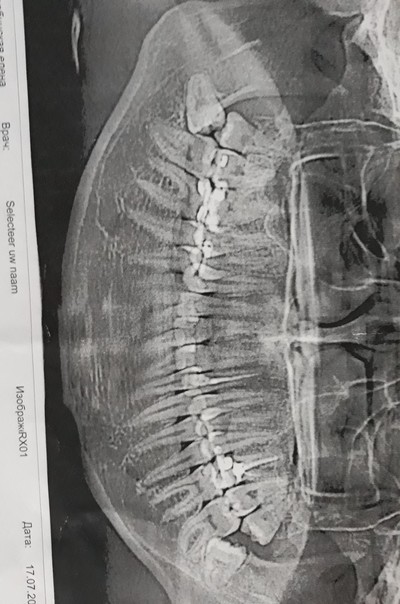

А для того, что ортопантомография (ОПТГ, обзорный или панорамный снимок зубов), является плоскостным, а значит происходит наложение каждой детали снимка послойно друг на друга. Следовательно, рассмотреть объект исследования, в частности, область зуба мудрости, расположенного рядом нижнечелюстного нерва, во всех плоскостях, под иным углом или другой проекции невозможно. КЛКТ (Конусно-лучевая компьютерная томография), напротив дает нам такую возможность.